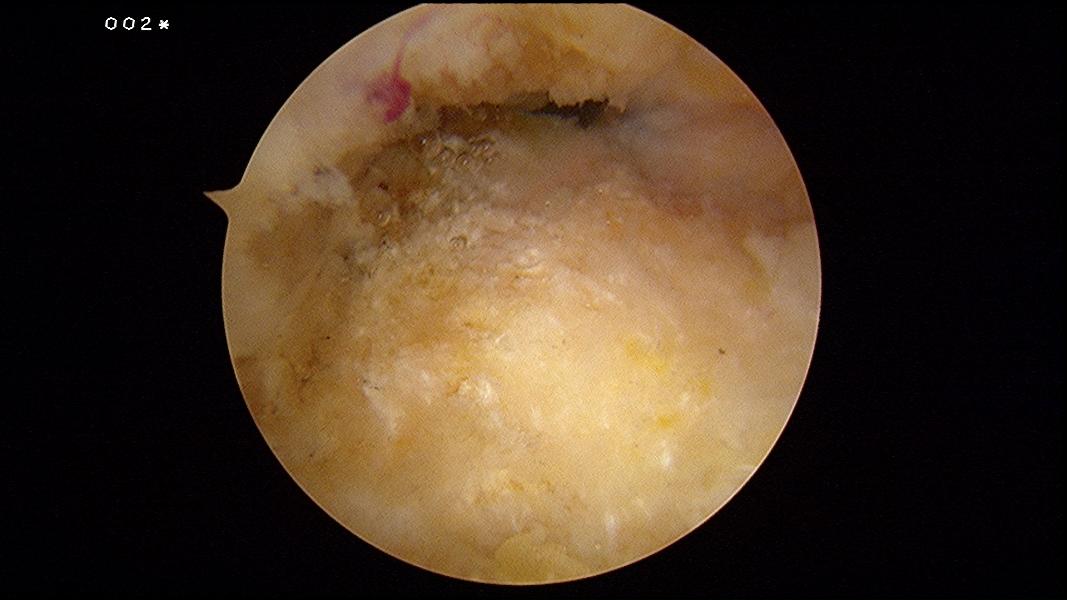

A small vertical incision is made through the skin at the level of the superior aspect of the calcaneus. The retrocalcaneal space is penetrated by a blunt trocar. A 4.5-mm arthroscope is introduced into the retrocalcaneal space.

Under direct vision a spinal needle is introduced just medial to the Achilles tendon, again at the level of the superior aspect of the calcaneus, to locate the medial portal. After making a vertical stab incision, the 3.5-mm full radius

resector is placed and visualized by the arthroscope. The inflamed retrocalcaneal bursa is removed to provide a better view.

The superior surface of the calcaneus is visualized, and its fibrous layer and periosteum is stripped off using a radiofrequency wand.

The Haglund’s exostosis is exposed.